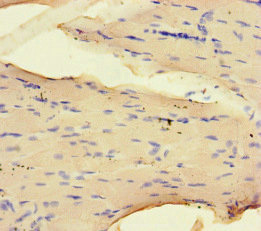

Immunohistochemistry of paraffin-embedded human skeletal muscle tissue using CSB-PA016092LA01HU at dilution of 1:100